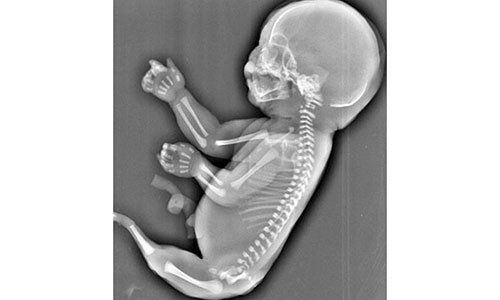

Theo đó, thai nhi "người cá" sáu tháng tuổi trên không có hai chân và lại "mọc đuôi" giống như người cá. Các bác sỹ cũng cho biết, thai nhi phát triển không bình thường trên cũng không có bàng quang và hai lá gan phát triển không đồng đều.

Theo các bác sỹ, thai nhi trên đã mắc phải hội chứng người cá, hay có tên khoa học là "Hội chứng Mermaid".

Hội chứng này gây ra dị tật bẩm sinh hiếm gặp khi hai chân hợp nhất với nhau. Nguyên nhân gây ra hội chứng Mermaid vẫn là một bí ẩn đối với y học thế giới. Tỷ lệ thai nhi mắc hội chứng này là 1/100.000.